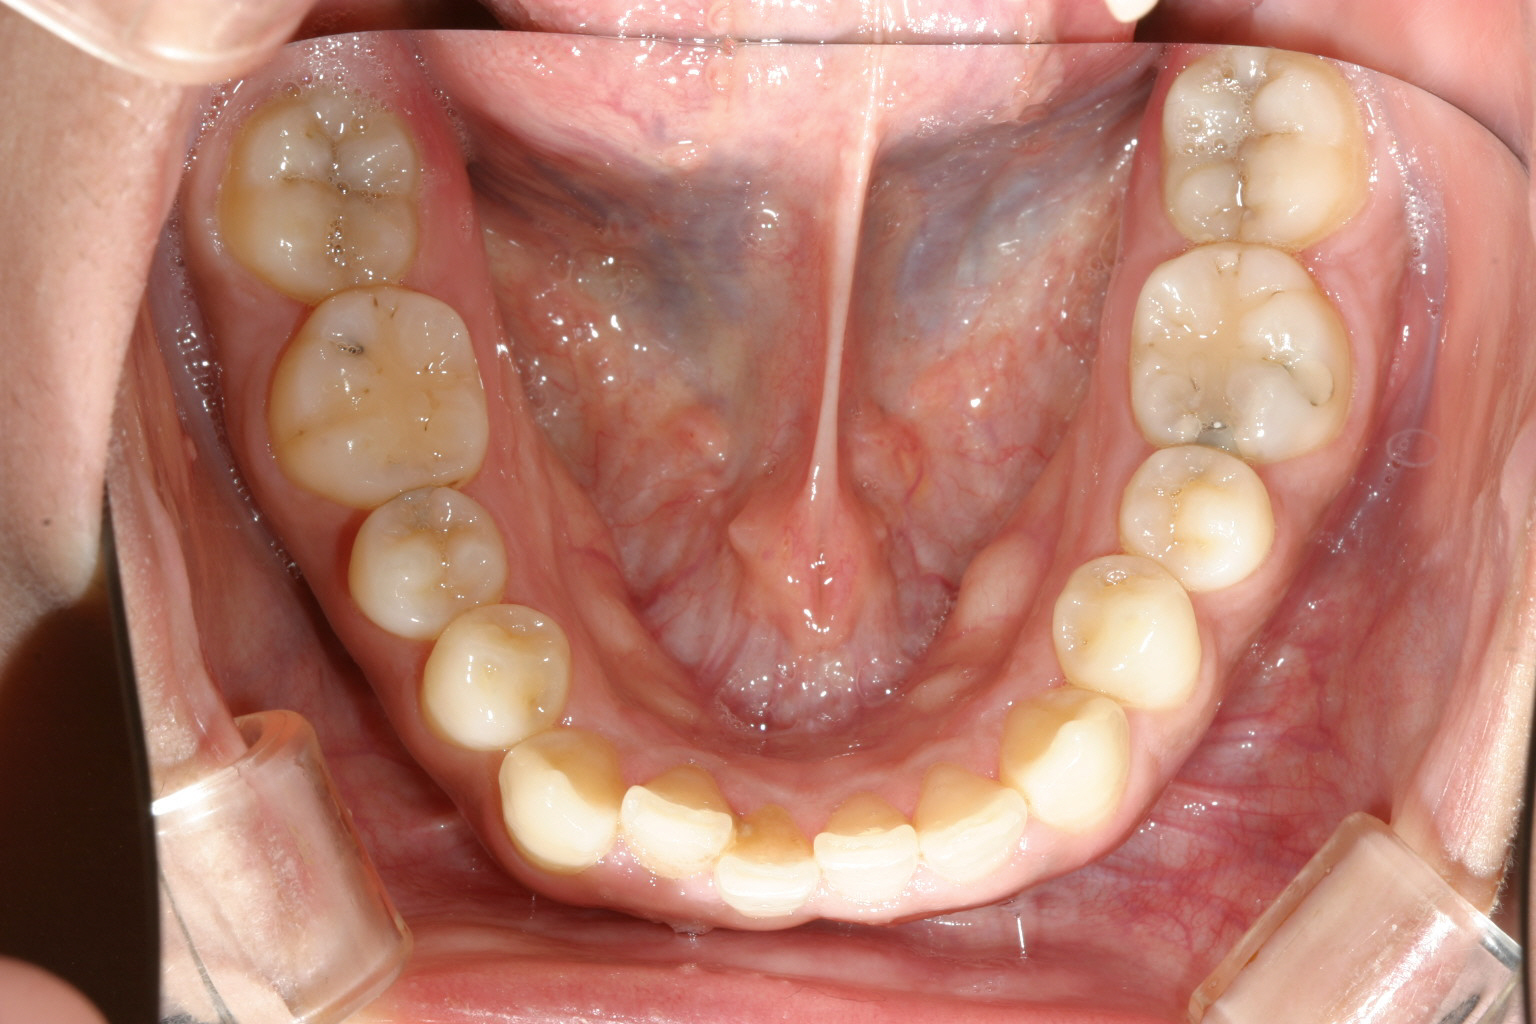

下顎もこんな感じです。綺麗でしょ?

このケースはあまりヘビーなケースでは無いですがこの当時インビザラインがまだこの世になかった時代の患者様でマルチループワイヤーを使用して治療致しました。

今なら典型的なインビザラインケースですね!